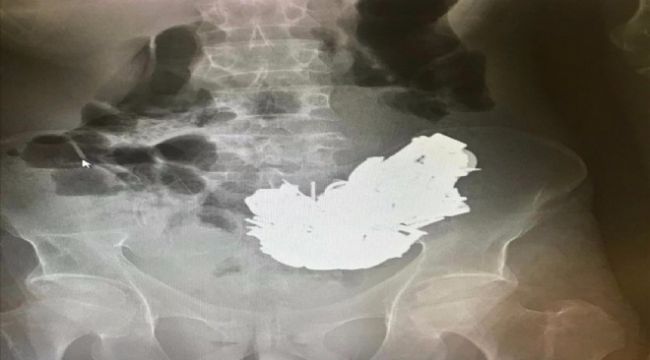

İzmir'de karın ağrısı şikayetiyle hastaneye götürülen ve midesinden 580 gram ağırlığında yaklaşık 200 cisim çıkarılan hasta kurtarılamadı. Bornova ilçesinde yaşayan 41 yaşındaki E.D, geçen hafta aniden rahatsızlanınca ailesi tarafından Ege Üniversitesi (EÜ) Tıp Fakültesi Hastanesi Acil Servisi'ne götürüldü. Doktorlar, röntgen filminde midede çok sayıda cisim bulunduğunu tespit etti.Sağlık durumu kötüleşen hasta için acil ameliyat kararı verildi. Hastanın midesindeki farklı boyutlarda ve toplam 580 gram ağırlığında yaklaşık 200 cisim, 3 saat süren ameliyatla alındı. Hastanın midesinden çıkarılan cisimler arasında bulunan mıknatıs, anahtar, boş kovan, çivi, cıvata, anahtarlık, madeni para, metal harfler ve çeşitli boyuttaki metaller, sağlık personelini şaşırttı.

Midedeki metallerin mıknatıs sayesinde bir arada toplanması, röntgen görüntüsüne de yansıdı. Operasyonun ardından yoğun bakım servisine alınan hasta, zehirlenmeye bağlı olarak hayatını kaybetti.EÜ Tıp Fakültesi Hastanesi Başhekimi Prof. Dr. Tuncay Göksel, AA muhabirine yaptığı açıklamada, bu tür vakaların daha çok küçük çocuklarda görüldüğünü ancak ilk kez bir yetişkinin midesinden bu kadar çok metal çıkarıldığına şahitlik ettiğini söyledi. Cerrahların hastayı kurtarmak için zamanla yarıştığını ancak hastaneye çok geç başvuran hastayı kurtarmakta başarılı olamadıklarını aktaran Göksel, "Midedeki metallerin çıkarılmasına rağmen metal ve mıknatısa bağlı zehirlenme nedeniyle hasta kurtarılamadı." dedi. (AA)